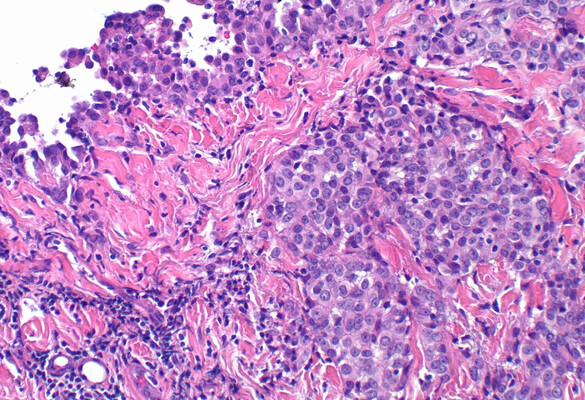

- The current invention describes an immune-oncolytic method by combining intratumoral administration of oncolytic modified vaccinia Tian Tan (MVTT) virus and depletion of myeloid-derived immunosuppressive cells (MDSCs) to induce protective T cell immune responses that exhibited dose-dependent effects in regression of solid tumors such as mesothelioma (AB1) and melanoma (B16F10).

Figure 1

D: Frequencies (left panel) and absolute numbers (right panel) of CFSE-labelled total MDSCs in both spleen and tumor 24 hours after treatment. Each mouse received 50 μl PBS or rMVTT (1 × 107 PFU).

F: Changes in the ratio of the PMN-MDSC proportion to the M-MDSC proportion were analyzed (left panel). PMN-/M-MDSC ratio measured before adoptive transfer was shown as baseline. Changes in the absolute numbers of M-MDSCs and PMN-MDSCs in the tumor are shown (right panel)